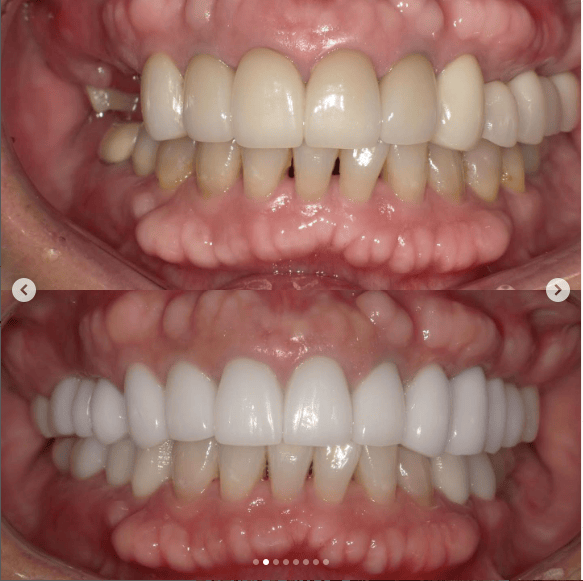

Case021 – インプラント

「ずっと放置してしまっていた。今回はちゃんとしっかり治したい」ということで、強い意志をもって来院してくださった患者様の症例です。

インプラント治療、セラミック治療、歯周病治療により、審美性と機能、咬みあわせの再建を行いました。

患者様は咬みあわせの確立により、食事もしやすく、普段の顎関節の状況も良くなり、機能の回復にも満足してくださり、また審美性も喜んでくださいました。

放置期間が長くだいぶ骨が溶けてしまっていたので、前歯部のインプラントは骨の再生療法などが必要だったりしましたが、患者様が治療への前向きな姿勢をだしてくださっていましたので期間も最短で終わりました。

一度放置してしまうと、億劫になってしまってなかなか行動に移すのは難しいと思いますが、少しでも早く治してあげた方が毎日の食事も楽になりますし、お顔の見栄えもお顔の骨格の歪みも改善します。

担当 理事長 佐藤 悠野